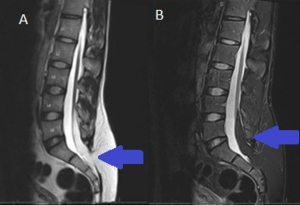

3 वर्षांपर्यंत वेगवेगवेगळ्या वेळी 17 डॉक्टरांना दाखविले, परंतु कुणालाच आजाराचे अचूक निदान करता आले नाही. अखेर कर्टनी यांनी मुलाच्या उपचारासाठी एआय टूल चॅटजीपीटीची मदत घेतली. त्यांनी मुलाच्या एमआरआर नोट्सना क्रमानुसार चॅटजीपीटीमध्ये प्लग गेले, चॅटजीपीटीने एलेक्स पालथा बसू शकत नसल्याचा निष्कर्ष काढला. यामुळे संरचनात्मक हिस्स्यात समस्या असून तो न्यूरोलॉजिकल सिंड्रोम ‘टेथर्ड कॉर्ड’ने ग्रस्त असल्याचे चॅटजीपीटीकडून कळले. यानंतर कर्टनी यांनी अन्य न्यूरोसर्जनसमोर

चॅटजीपीटीकडून प्राप्त निष्कर्ष मांडला.

चॅटजीपीटीने काढलेला निष्कर्ष अचूक असल्याचे डॉक्टरांना आढळून आले. याप्रकरणी डॉक्र एमआरआर नोट्सद्वारे एलेक्सच्या कण्यामध्ये समस्या कुठे आहे हे शोधून काढण्यास समर्थ होते. परंतु त्यांना ते जमले नव्हते. एलेक्सच्या कण्याच्या हाडावर शस्त्रक्रिया झाली असून आता त्याची प्रकृती सुधारत आहे.